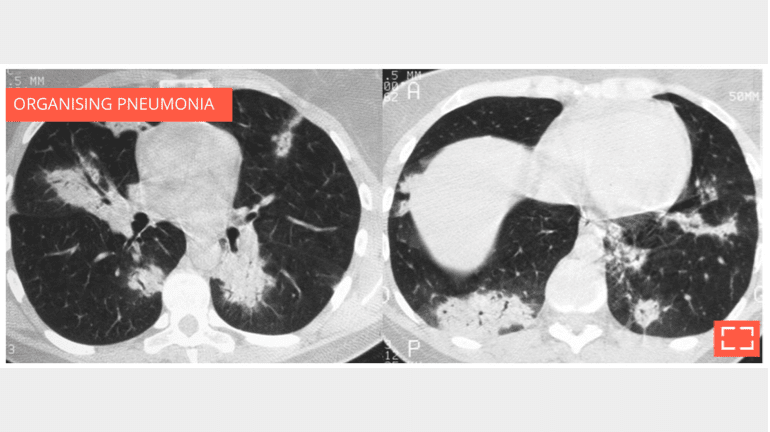

Bilateral subpleural alveolar consolidation with air bronchogram, in a patient with chronic cough.

• Note whether the foci migrate between the two scans, strengthening the argument for organising pneumonia.